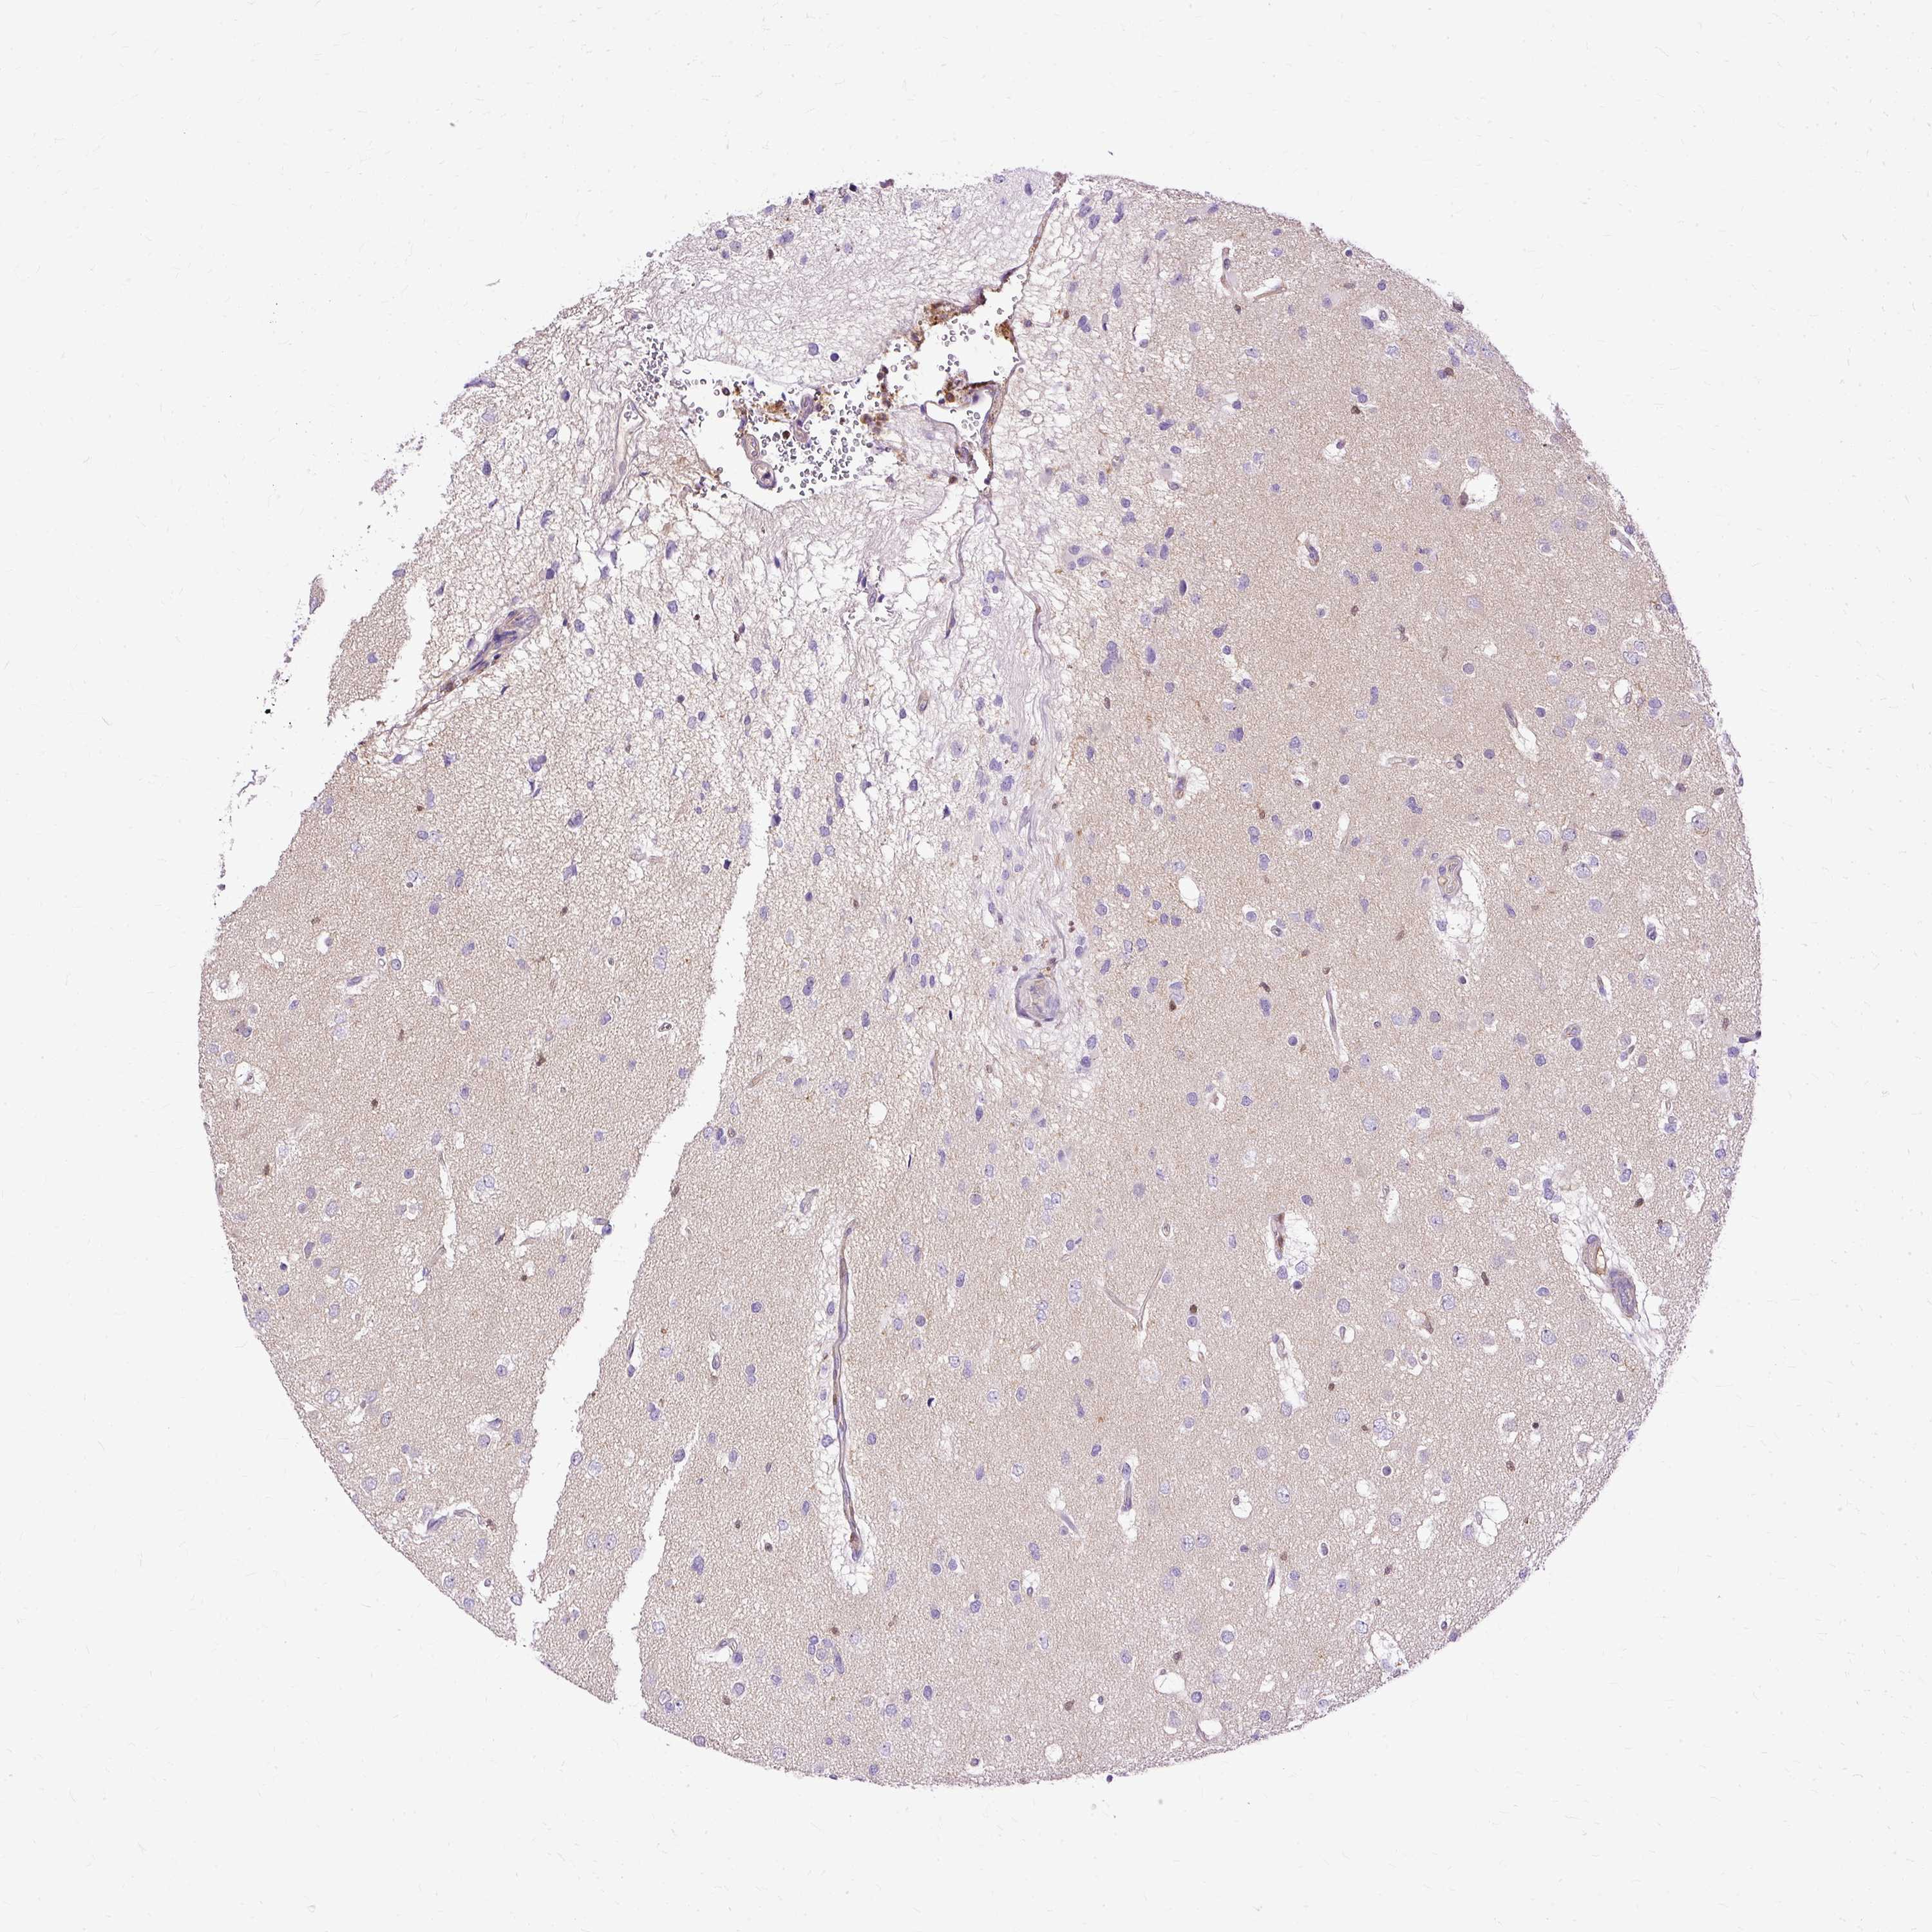

GLIOMA - Protein expressioni

A mouse-over function shows sample information and annotation data. Click on an image to view it in a full screen mode. Samples can be filtered based on level of antibody staining by selecting one or several of the following categories: high, medium, low and not detected. The assay and annotation is described here.

Note that samples used for immunohistochemistry by the Human Protein Atlas do not correspond to samples in the TCGA dataset.

Antibody stainingi

Antibody staining in the annotated cell types in the current human tissue is reported as not detected, low, medium, or high, based on conventional immunohistochemistry profiling in selected tissues. This score is based on the combination of the staining intensity and fraction of stained cells.

Each image is clickable and will lead to virtual microscopy that enables deeper exploration of all samples and also displays staining intensity scores, fraction scores and subcellular localization as well as patient and tissue information for each sample.

Antibody HPA053874

Staining

High

Medium

Low

Not detected

Intensity

Strong

Moderate

Weak

Negative

Quantity

>75%

75%-25%

<25%

None

Location

Nuclear

Cytoplasmic/membranous

Cytoplasmic/membranous,nuclear

Glioma, malignant, Low grade

Glioma, malignant, High grade